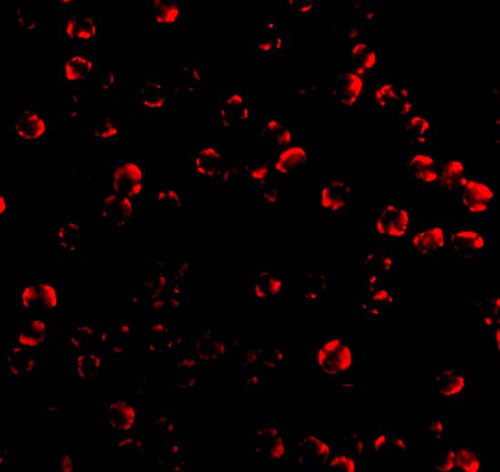

Immunofluorescence of Caspase 6 in MCF7 cells with Caspase 6 antibody at 10 μg/mL. |